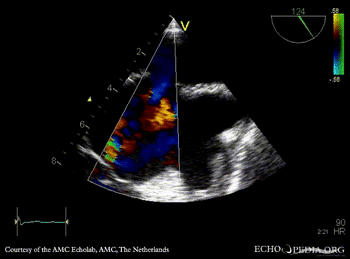

E00310.gif E00311.gif

Subcostal view: ASD type II TEE: ASD type II